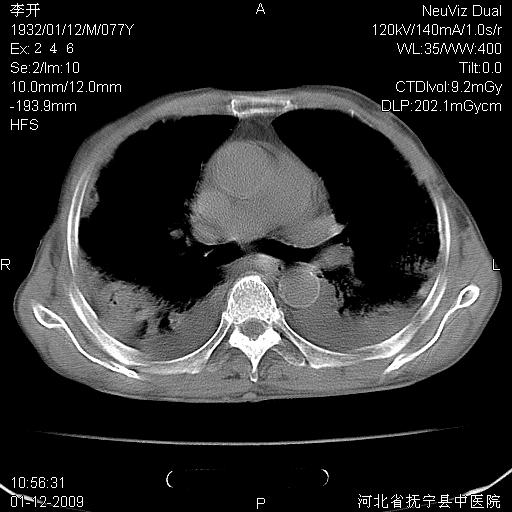

以下是引用黑白光影在2009-1-19 16:49:00的发言:[br]心衰肺水肿;心包、胸腔积液;冠脉钙化;肺部感染。